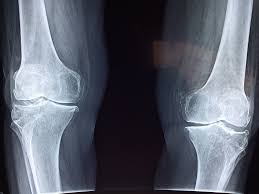

Vos os méritent mieux que cela

Un aspect souvent négligé : l’impact des sodas, et particulièrement des colas, sur la solidité de notre squelette. Le problème ne vient pas nécessairement d’un composant unique, mais plutôt du fait qu’ils remplacent des boriches essentielles comme le lait ou les alternatives végétales enrichies en calcium. Chez les adolescents et jeunes adultes, cette substitution peut compromettre la construction d’une ossature robuste. Chez les adultes, elle participe à une fragilisation osseuse progressive sur le long terme.